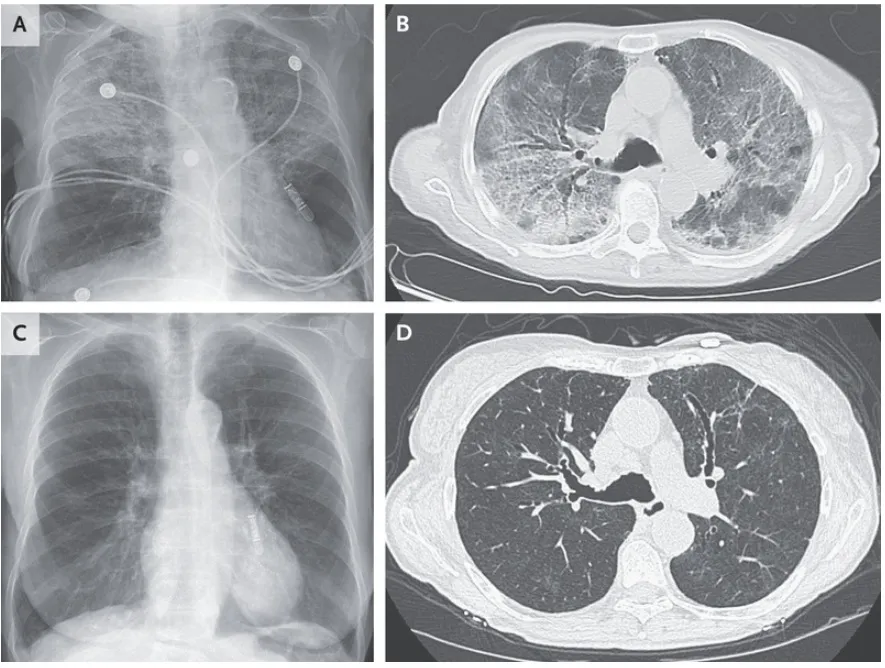

En la evaluación de laboratorio, se observó una leucocitosis neutrofílica, pero sin eosinofilia. En la radiografía de tórax se observaron opacidades alveolares irregulares más prominentes en los lóbulos superiores (Panel A). Los cultivos de esputo y el panel respiratorio viral resultaron negativos. La imagen de tomografía computarizada de tórax mostró vidrio esmerilado y opacidades reticulares con predominio en el lóbulo superior y bronquiectasias moderadas (Panel B). Debido a los hallazgos de imagen y a la exposición prolongada a la nitrofurantoína, se realizó el diagnóstico de lesión pulmonar crónica inducida por nitrofurantoína.

En pacientes con lesión pulmonar inducida por nitrofurantoína, los hallazgos radiológicos son variados y pueden distribuirse de manera difusa o localizada. Se suspendió el tratamiento con nitrofurantoína y se recetó prednisona, observándose una mejoría en el cuadro clínico después de una semana y una resolución radiográfica después de dos meses (Paneles C y D, respectivamente).